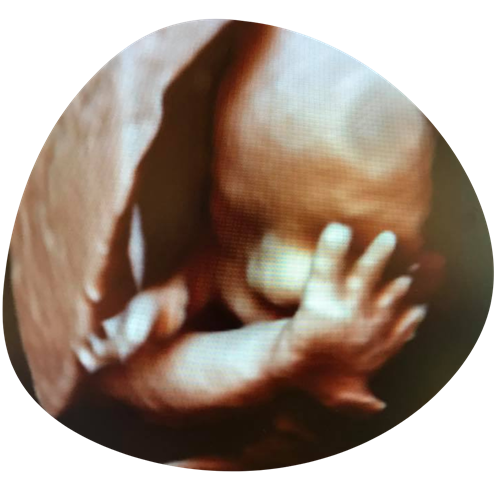

3/4D echo

Een bijzondere echo waarbij jouw ongeboren kind haarscherp en realistisch in beeld wordt gebracht. Je ziet niet alleen de contouren, maar ook het volume van je baby. Heeft hij/zij bolle wangetjes en op wie lijkt hij/zij eigenlijk? Soms zie je ook echt al de mimiek tijdens de echo: boos kijken, lachen, pruilen of even gapen…

€90 (30 minuten)